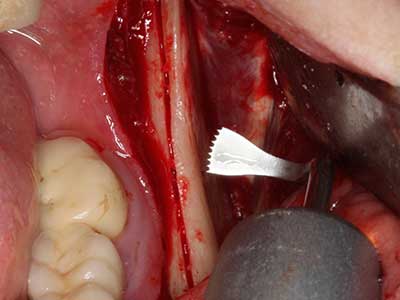

Fig. 17a: CT image of a growth-promoting osteotomy immediately adjacent to ...

Abb. 17b: the alveolar duct with nerve irritation (lateral and coronal view).

Fig. 18: Preparation of a cortical cover with the piezo bone saw (Piezomed, W&H).

Fig. 19: Surgical site after neurolysis and removal of osteoma.

Fig. 20: The removed bone cover is re-adapted and fixed with an osteosynthesis screw (KLS Martin, Tuttlingen).